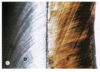

e - enamel

d - dentin

c - cementum

d - dentinal tubules

e - enamel rods (prisms) of calcium hydroxyapatite

black - cementum

red - dentin